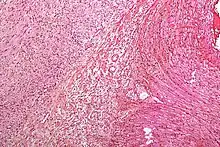

Cell morphology observed in all nerve root schwannomas

Trigeminal schwannoma is a condition in which a tumor forms on the trigeminal nerve (also known as cranial nerve five).[1] This prevents sensation in the area associated with the nerve. In the case of the trigeminal nerve, this is the face, meaning hypoesthesia of the face is experienced. Excision is the only effective treatment of trigeminal schwannoma, though this may not treat the associated hypoesthesia if damage has already occurred. Following surgery, many patients still experienced hypoesthesia and some even experienced increased effects.[1]